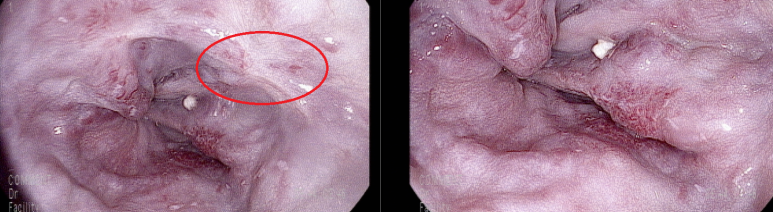

이번 검진 내시경, 이전과 같은 위치에 결찰술 흔적

하부 식도에 추가로 결찰술한 흔적

그러나 전체적으로 LsF3CbRCS(+++) 정도의 소견은 변화없음

내시경시 구역만으로도 출혈이 시작될 수 있는데 검진을 받으로 오는거나 왔다고 처방을 내는거나 다 문제가 있다. 의원에서 출혈시 EVL용 밴드나 Sengstaken–Blakemore tube 가 없기 때문에 응급처치나 치료를 할 수 없다. F3에 red color change가 심한 경우에는 상황에 대비할 수 있는 곳에서 검사를 받는 것이 바람직하다.

현재의 의학적 문제에서 굳이 검진 내시경을 받길 원하면 대학병원에서 받아야하고, 본인이 직접 검사할 것이 아니라면 환자에게 그렇게 안내(Nudge)하기를 주치의에게 알려주었다.